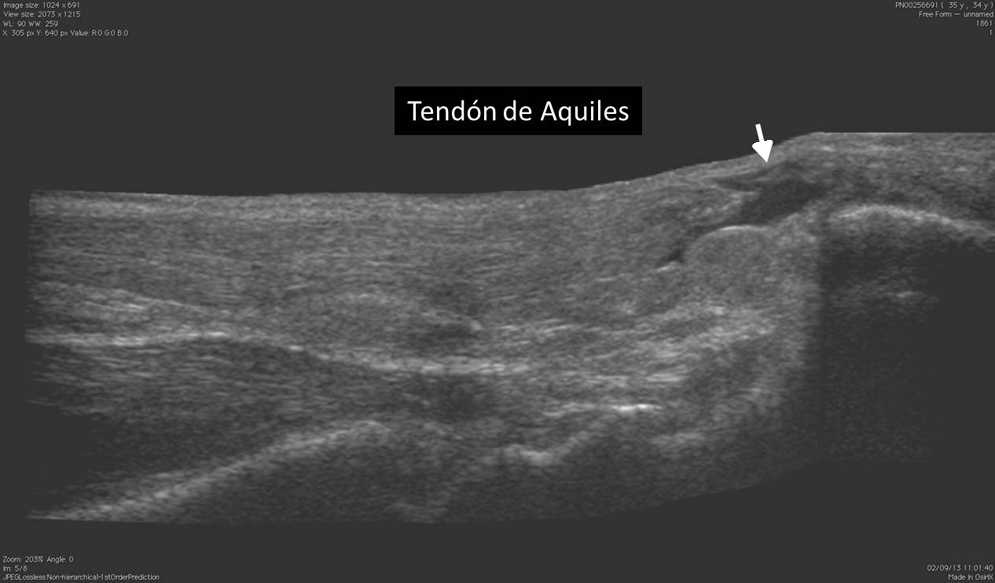

La ecograf??a es el m??todo ideal para la exploraci??n del sistema musculoesquel??tico, en tanto brinda la posibilidad de evaluarlo en reposo o en movimiento, observando los cambios en tiempo real. Adem??s, permite la comparaci??n del sitio exacto del dolor con su lado contralateral, adquiriendo im??genes en panor??mica19.

Los actuales transductores de alta frecuencia (12-18 MHz) tienen excelente resoluci??n para analizar las estructuras superficiales (m??sculos, tendones, ligamentos y bursas) y sus patolog??as20 (figs. 14 y 15). La ecograf??a en escala de grises permite una gran imagen anat??mica de la lesi??n, mientras que el Doppler color identifica la vascularizaci??n del tejido y las im??genes panor??micas otorgan una visualizaci??n extensa del campo de visi??n, que muestra la lesi??n y su relaci??n con las estructuras vecinas (fig. 16).